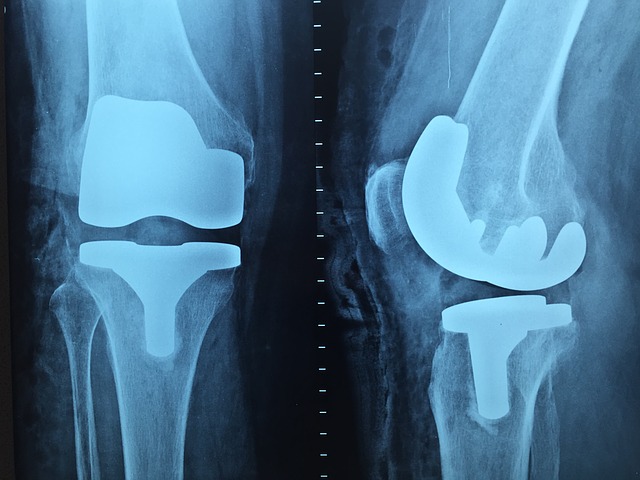

Наша клиника является сертифицированным центром эндопротезирования.

Центры эндопротезирования ежегодно проверяются независимыми институтами в отношении проведения процедур дооперационных и послеоперационных услуг и гигиенических норм. Центр сертификации endoCert подтвердил, что Центр эндопротезирования в Дюссельдорфе во всех этих областях соответствует высоким стандартам. Особое признание получено в области профилактики инфекций, благодаря тому, что здесь  задействован специалист по вопросам гигиены, который осуществляет последовательной контроль MRSA (метициллин-резистентный золотистый стафилококк) перед предстоящими операциями.

Особенности Центра эндопротезирования:

• Стандартизация процессов: от первого врачебного приема до момента выписки пациента для последующего прохождения реабилитации

• Врачебная консультация по вопросам эндопротезирования как ни к чему не обязывающий консультационный пункт для пациентов

• Подготовка и подробное информирование пациентов перед операцией

• Предложенный ассортимент методов операций, хорошо зарекомендовавших себя в эндопротезировании

• Стандарты лечения в период последующего/послеоперационного лечения:  медицинский уход, совмещенный с сеансами физиотерапии.

• Врачи и весь медицинский персонал постоянно повышают свою квалификацию и профессиональную переподготовку на германских и интернациональных курсах повышения квалификации.